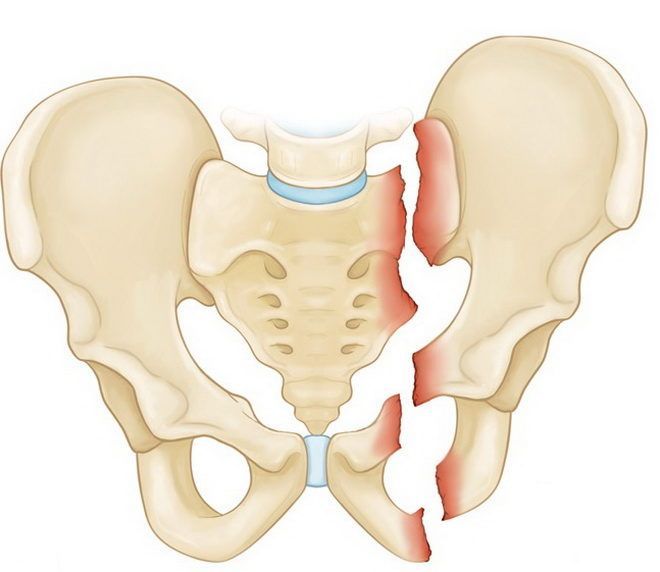

- перелом кости со смещением. Наблюдается нарушение целостности тазового кольца,

Односторонний перелом седалищной и лонной костей таза

Двусторонние переломы лонной и седалищной костей